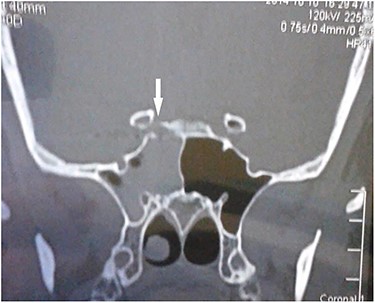

Computed tomography (CT) of the paranasal sinuses and angiography were requested on an urgent basis, which confirmed a diagnosis of pseudoaneurysm in her right CCA, adjacent to retained pellets (Figs 1–4). Also, her hemoglobin dropped from 11.5 to 8.4 gm over a 6-month period. Afterwards, she was referred to the interventional radiology department. She underwent stenting and coiling of her right internal carotid artery after which no further epistaxis happened for an uneventful year of follow-up.

CT scan coronal view showing right sphenoid sinus opacification with denudation of sphenoid sinus wall (arrow).